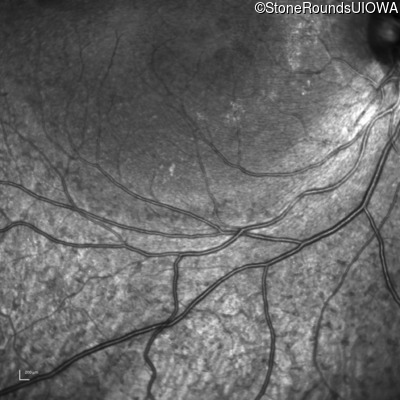

Infrared Fundus Photograph - Left - 20/25

Exemplar